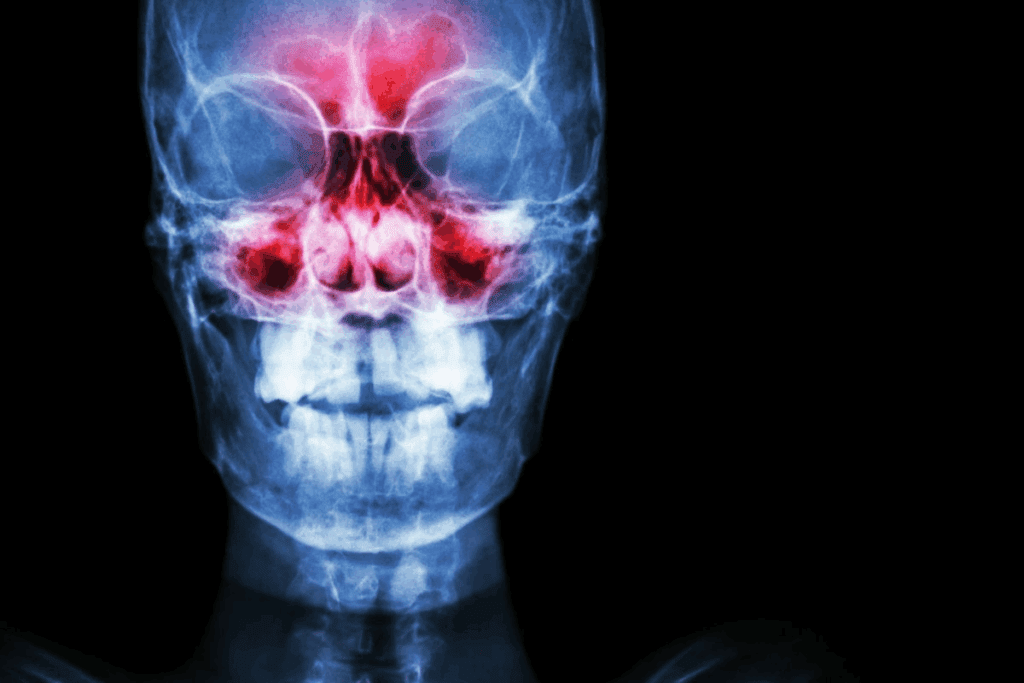

Bloody sinusitis is a severe sinus infection. It happens when inflammation is so bad it breaks blood vessels in the nasal passages and sinuses. This can lead to sinus infection blood clots mucus.

Bloody sinusitis happens when sinuses get inflamed or infected. This leads to blood in the nasal discharge. It can be caused by bacterial, viral, or fungal infections, or allergic reactions.

The inflammation makes the sinus lining swell. This can burst small blood vessels, causing bleeding.

The start of bloody sinusitis is inflammation in the sinus tissues. When the sinuses get infected, the lining swells and makes more mucus. This makes the blood vessels in the sinus lining weak and more likely to break.

The breaking of blood vessels in the sinuses is a key part of bloody sinusitis. When the blood vessels are weak from inflammation, even a little pressure or injury can make them break. This leads to bleeding in the sinus cavity.